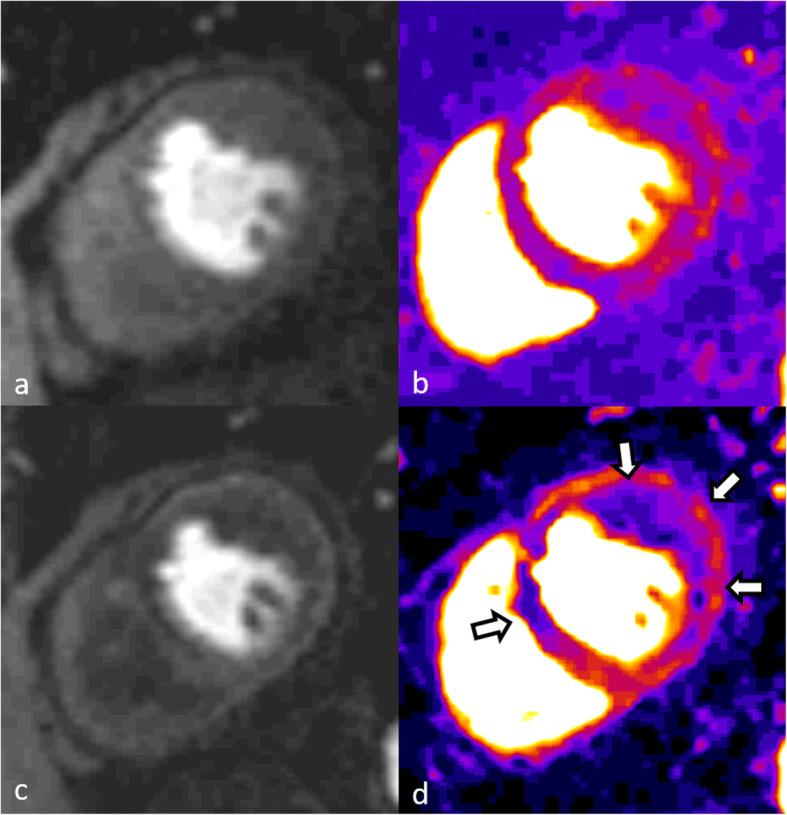

Ischemic heart disease and its sequelae are one of the major contributors to morbidity and mortality worldwide. Over the last decades, technological developments have strengthened the role of noninvasive imaging for detection, risk stratification, and management of patients with ischemic heart disease. Cardiac magnetic resonance (CMR) imaging incorporates both functional and morphological characterization of the heart to determine presence, acuteness, and severity of ischemic heart disease by evaluating myocardial wall motion and function, the presence and extent of myocardial edema, ischemia, and scarring. Currently established clinical protocols have already demonstrated their diagnostic and prognostic value. Nevertheless, there are emerging imaging technologies that provide additional information based on advanced quantification of imaging biomarkers and improved diagnostic accuracy, therefore potentially allowing reduction or avoidance of contrast and/or stressor agents. The aim of this review is to summarize the current state of the art of CMR imaging for ischemic heart disease and to provide insights into promising future developments.

缺血性心脏病及其后遗症是全球发病率和死亡率的主要原因之一。在过去的几十年中,技术的发展增强了无创成像在检测、风险分层和缺血性心脏病患者管理方面的作用。心脏磁共振(CMR)成像结合了心脏的功能和形态特征,通过评估心肌壁运动和功能、心肌水肿、缺血和瘢痕的存在和程度,来确定缺血性心脏病的存在、急性和严重程度。目前已建立的临床方案已经证明了其诊断和预后价值。然而,新兴的成像技术基于对成像生物标志物的高级定量和提高的诊断准确性提供了额外的信息,因此有可能减少或避免使用对比剂和/或应激剂。本综述的目的是总结 CMR 成像在缺血性心脏病中的最新技术,并探讨有前途的未来发展方向。